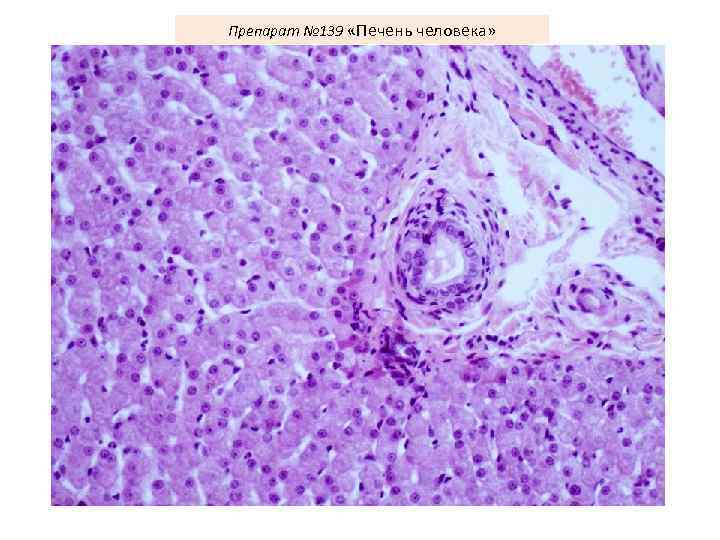

Препарат № 139 «Печень человека»

Препарат № 139 «Печень человека»

Препарат № 139 «Печень человека»